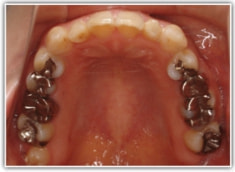

治療前